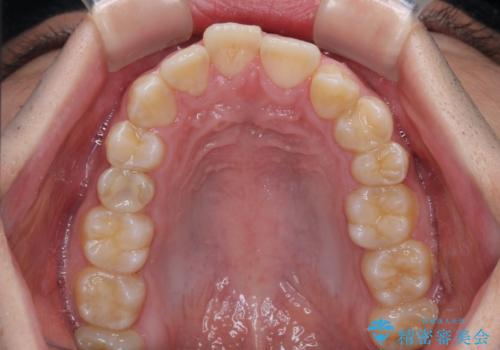

- デコボコと奥歯の咬み合わせのズレを気にして来院された患者様です。

骨格的に、下顎が右側にずれており、左側の咬み合わせに鋏状咬合などのアンバランスが生じている状態でした。

また、上顎前歯に欠損が1本あり、上下ともに前歯部に叢生が認められ、下顎前歯の大半が隠れてしまうほどの過蓋咬合も認められました。

骨格的な左右差が大きかったため、上下の正中のズレや、左右奥歯の咬み合わせなどは妥協的な仕上がりとなりました。

骨格的なズレに対応するにはワイヤー矯正が至適であり、マウスピース矯正は選択しないようにお話をしました。